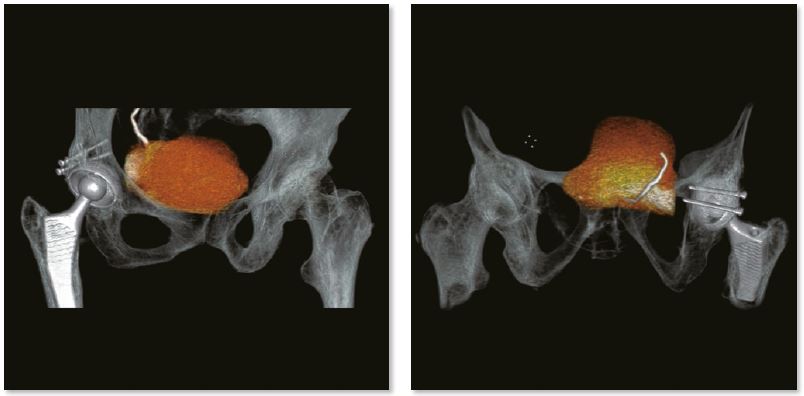

Обстеження м'яких тканин тазу

SEMAR можна вільно застосовувати, проспективно чи ретроспективно, до отриманих необроблених даних під час сканування будь-якого обсягу. У цьому випадку SEMAR застосовували для зниження металевих артефактів і отримання чіткого огляду м’яких тканин малого тазу. Пухлина сечового міхура чітко видно на реконструйованих зображеннях SEMAR.

3D зображення тазу

Звичайне зображення

Зображення з SEMAR